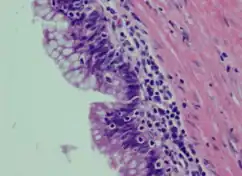

| Atypical goblet cells with focal tufting. | |